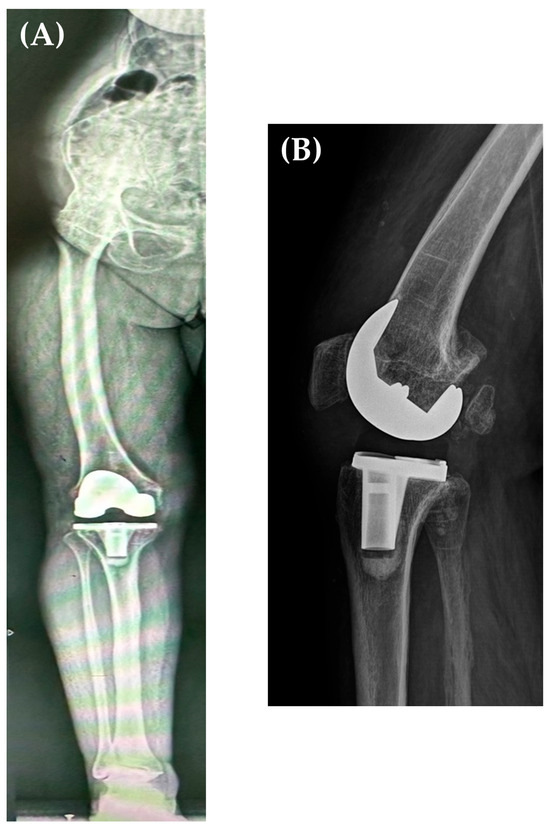

Postoperative X-rays revealed adequate positioning and sizing of the prosthetic components and a restored alignment of the lower limb. Personalized rehabilitation was initiated 24 h after the surgery, with knee flexion being recovered at the edge of the bed, and knee extension in lateral decubitus; weight bearing was allowed on the 1st postoperative day, and the patient started walking with the aid of crutches. Subsequent periodic radiological follow-ups at 3, 6, 12 months and annually up to 5 years (Figure 6A,B) did not show any signs of loosening (Figure 3). At her 3-month follow-up, the patient had an active range of motion (ROM) of 110° knee flexion and full extension (in lateral decubitus), walking without any aiding devices, with an increase in KSS from 26 to 84 points and WOMAC increase from 40 to 77.

Figure 6. Five years postoperative AP long leg X-ray (A) and sagittal X-ray (performed at 30° of knee flexion) (B) showing the correct alignment of the femoral and tibial prosthetic components, neutral alignment of the right lower limb, and no component loosening.